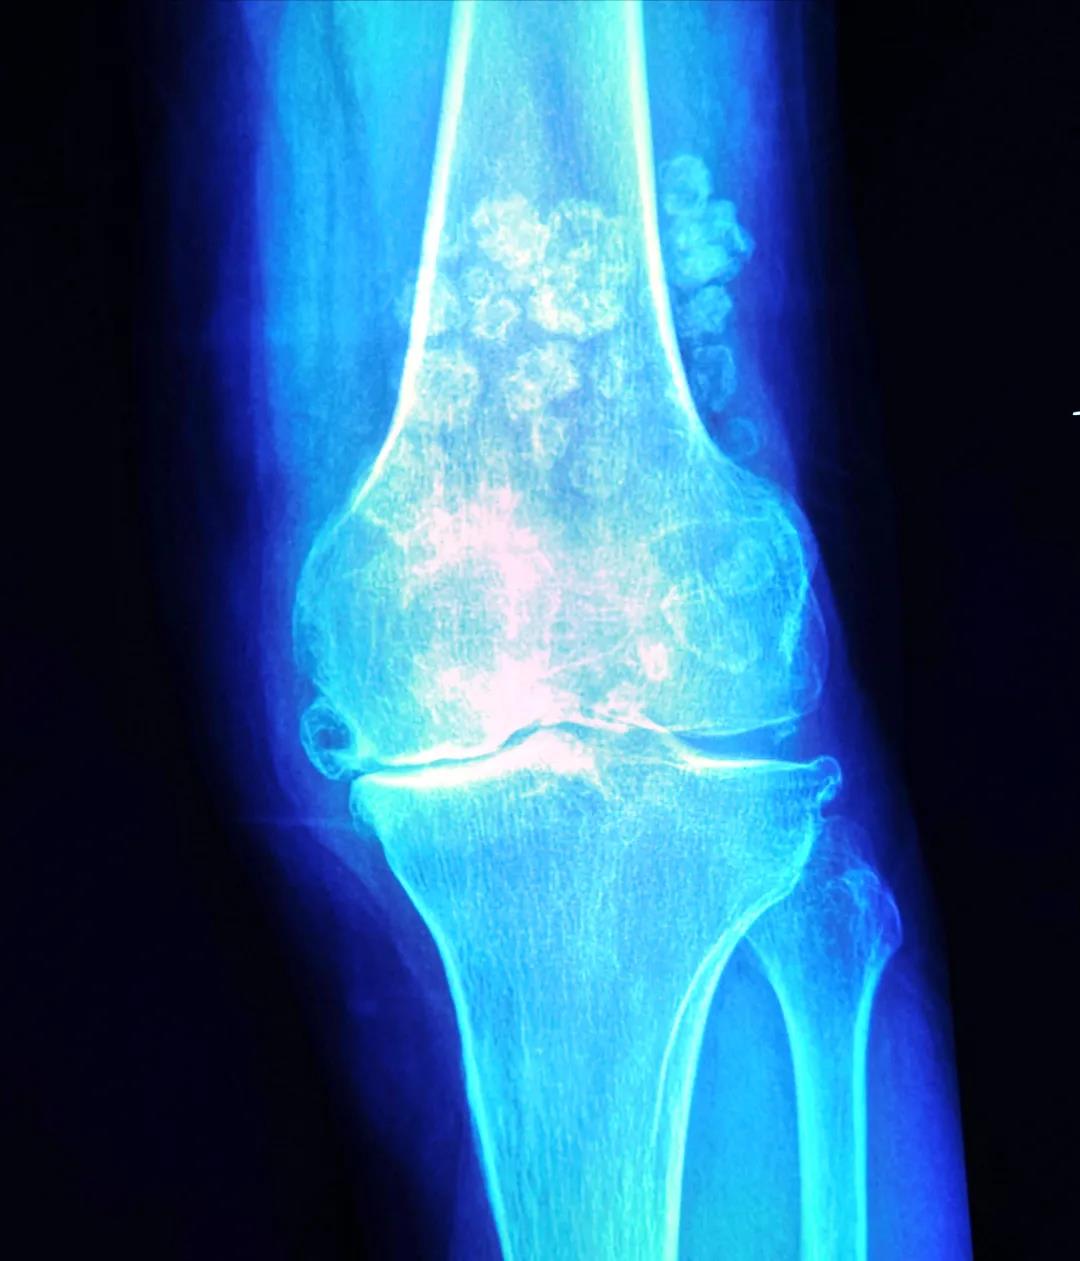

来自青海农村的68岁的李婆婆,由于长年累月的繁重农活,饱受双膝疼痛15年,从40多岁就不能利索地行走了。近3年病情加重无法行走,一度卧床休息几个月。到当地各地医院求诊,均因严重的“滑膜软骨瘤病”,医生都难以为其手术治疗。后经多方打听,家人得知新桥医院骨科擅长治疗此类疾病,并且还能通过微创精准的方式完成膝关节置换手术,所以不远千里前往重庆就诊。

张瑗副教授在接诊李婆婆后,经过详细的术前检查,判断能通过人工膝关节置换为其解除病痛,且能借助最新的机器人辅助外科手术系统,进一步提高膝关节置换的手术精准度,随即决定邀请这位“新人”为李婆婆一同手术。

强大的数据计算处理系统是这位“新人”的大脑,能将术前采集到的患者影像信息和医生手术方案精确计算和设计,得出手术中需要完成截骨、膝关节置换等手术数据和路径。术中导航系统作为这位“新人”敏锐的“双眼”,能引导它的一只“巧手”(机械臂),精准完成截骨等操作。经过经两小时手术,专家们在这位“新人”助力下,理想重现了术前规划并完成手术,免除了传统工具带来的扩髓和松解操作带来的手术创伤,实现了机械力线、解剖重建和微创理念的三重目标。